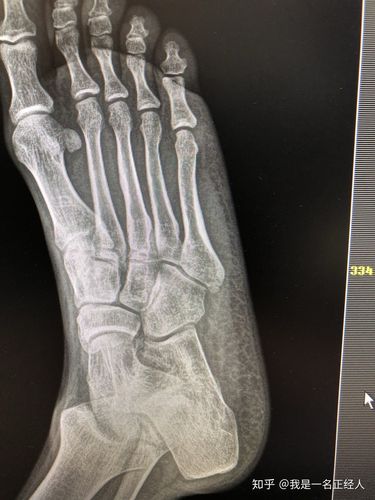

先天性第四跖骨短小症

脚趾短小怎么办?

一次性手术治疗先天性跖骨短小症